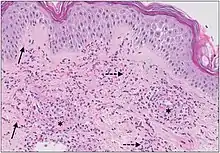

| Urticaria, lymphocyte predominant | Perivascular location. Mast cells are relatively sparse, potentially demonstrated with special stains, preferably tryptase stain. Extravasated erythrocytes are present in about 50% of the cases. No vasculitis.[14] | Dermal edema [solid arrows in (A,B)] and a sparse superficial predominantly perivascular and interstitial infiltrate of lymphocytes and eosinophils without signs of vasculitis (dashed arrow).[15] |

![]() |